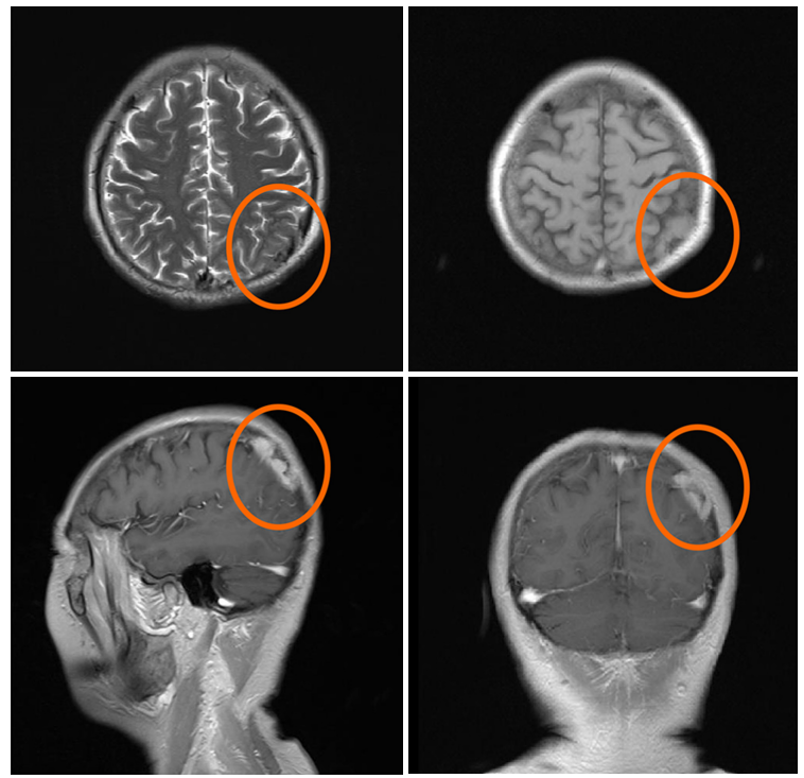

长期治疗难免出现不良反应:2022 年初,患者出现 1-2 级外周水肿(MET 抑制剂常见副作用),起初通过 “低盐饮食 + 肢体抬高” 缓解,未调整药量;2022  4 月,水肿加重至级(严重影响生活),医生没有盲目停药,而是先做了ctDNA 检测(MRD 监测) —— 结果显示 ctDNA 阴性。基于这个关键结果,医生大胆调整方案:将赛沃替尼剂量从 600mg /天减至 400mg / 天,吉非替尼剂量不变。调整后,水肿迅速缓解至 1 级,且后续多次复查(2023 月、2025  1 月):

CT 显示肿瘤持续稳定(SD),无进展;

ctDNA 始终阴性;

截至 2025  4 月,患者的无进展生存(PFS)已超过 8 年。

图片

治疗期间的胸部 CT 随访图像。图像中的绿色线条表示肿瘤病灶的测量直径。